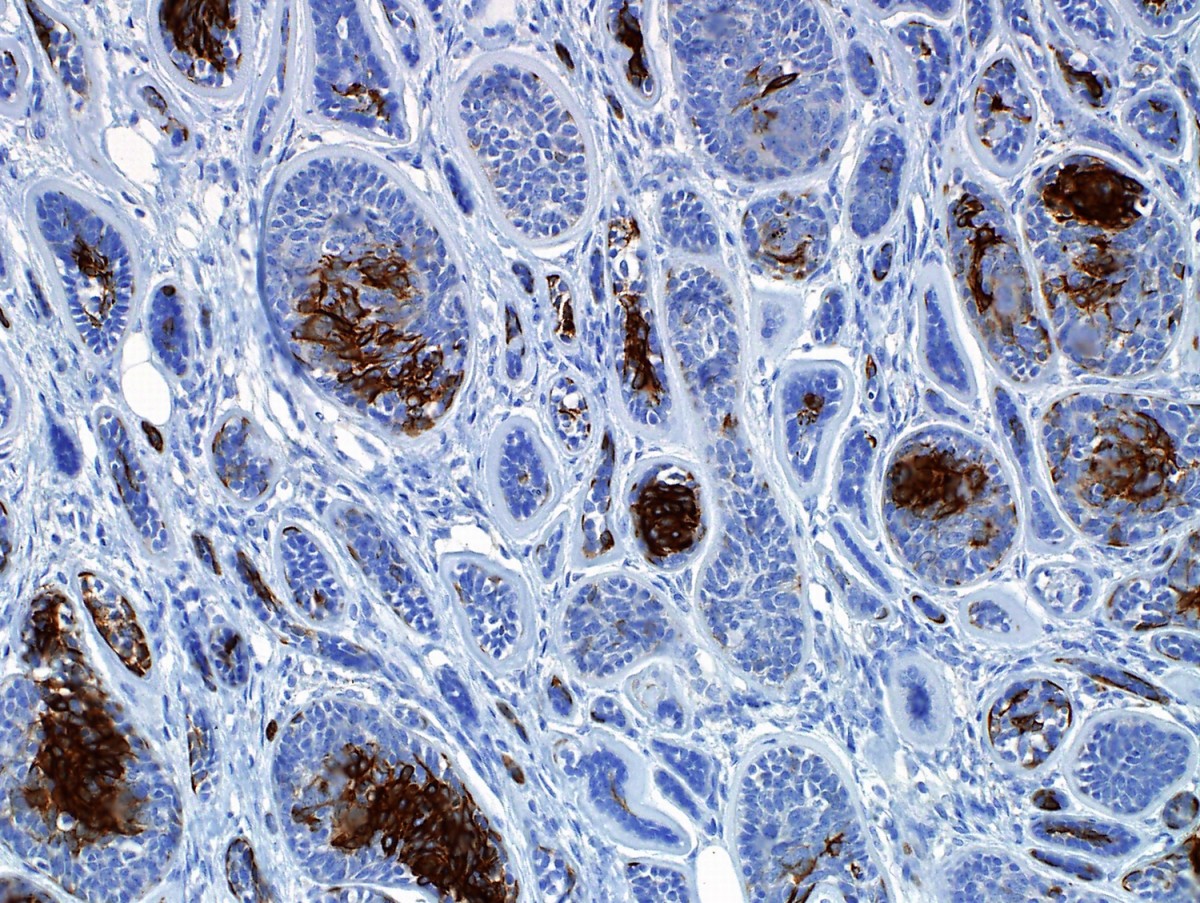

Immunohistochemistry (IHC) is a vital technique in pathology and biomedical research that allows the visualization and localization of specific proteins or antigens in tissues. By utilizing antibodies that bind to target molecules, IHC enables researchers to gain insights into cellular structure and identify disease markers. This powerful tool plays a crucial role in cancer diagnosis, personalized medicine, and understanding various diseases at a molecular level, contributing significantly to advancements in medical science.

Pathology and molecular biology both make extensive use of the method of immunohistochemistry to reveal important details about cellular makeup, operations, and pathological states. So, immunohistochemistry is widely used in biomedical research in several fields, including cancer research, medication development, and diagnostic pathology.